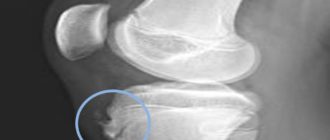

Воспаление бугристости большеберцовой на обеих ногах у взрослого

Болезнь Осгуда-Шляттера, чем опасна бугристость большеберцовой кости? Заболеванием Осгуда-Шляттера называются патологические изменения в коленном